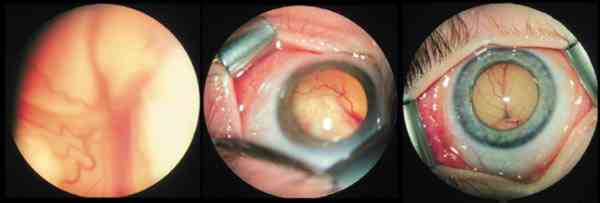

las zonas problemáticas.    Crioterapia, cerclaje e implante sin punción de bolsa subretiniana en un

desprendimiento de retina de un retinoblastoma.

espontánea ante nuestra sorpresa.  El procedimiento quirúrgico en el desprendimiento pasa por realizar

cerclajes e implantes que taponen las zonas problemáticas (59). La punción del

líquido subretiniano está en discusión permanente por el riesgo de actividad

y diseminación de células tumorales durante la cirugía. En los tratados con

quimioterapia, 1 mes puede ser tiempo suficiente en nuestra experiencia para que

afloren nuevos focos y siembras. Con radiación hay que esperar más. De

cualquier forma se pueden intentar procedimientos externos sin punción a los 30

días de diagnosticados, aunque no se visualicen los desgarros y reservar los

drenajes y las vitrectomías para más adelante dependiendo de las posibilidades

de visión y de si son ojos únicos o no (56-60).  El drenaje del fluido subretiniano debe ser analizado por Citología,